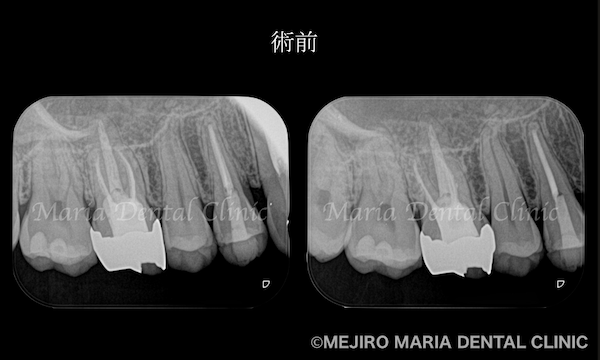

を併発した根尖性歯周炎を、精密根管治療で治癒|術前の歯のレントゲン画像_治療前1.png)

患者様は1年前に、右上4番の歯に違和感を覚え、近隣の歯科医院にて初めての根管治療(抜髄処置)を行うも、症状が改善されませんでした。その後、他の歯科医院に相談するも、症状の原因となる歯の特定には至ることができず、目白マリア歯科を受診されました。

患者様ご自身は、1年前に根管治療を行った右上4番の歯の予後不良を疑っていました。しかし当院の診査にて、患者様の訴える症状の原因は、数年前に根管治療を行った右上6番の歯の予後不良による根尖性歯周炎と診断しました。

治療詳細

治療のコンセプトに沿って精密根管治療を2回で終了させ、暫間冠(仮歯)にて3ヶ月間の経過観察を行いました。3ヶ月後には症状は完全に消失、セラミック冠を装着して今後2年間の経過観察を行うこととしました。